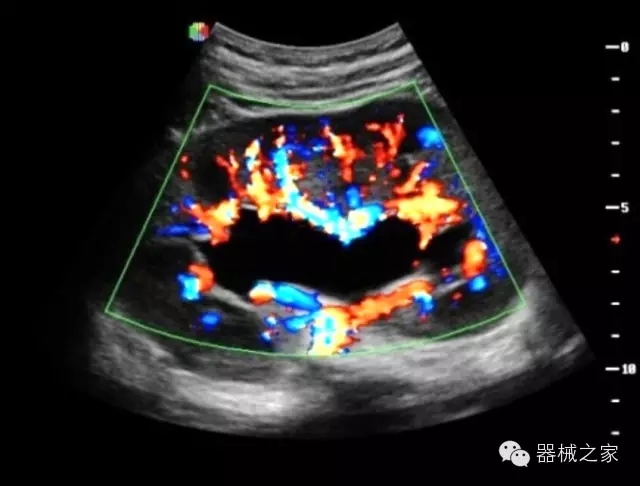

臨床圖片賞析

產(chǎn)品特點

·獨有的RF平臺提高微小細節(jié)顯示、圖像對比度和邊界清晰度;

·特有的XCEN探頭,超寬的帶寬,表現(xiàn)更高分辨率和對比度;

·單晶純凈波探頭提供更佳的穿透力和彩色敏感度;

·完整的3D/4D臨床應用,STIC, MCUT 和Auto NT等滿足產(chǎn)科所有應用;

·更高的HQ羊膜腔鏡成像技術(shù)精細觀察每一個暗區(qū)細節(jié);

·獨有RF敏感血流使得心臟血流完美呈現(xiàn);